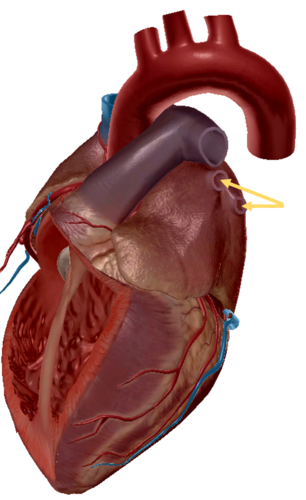

aorta

aortic trunk

pulmonary semi-lunar valve

aortic trunk

aortic semi lunar valve